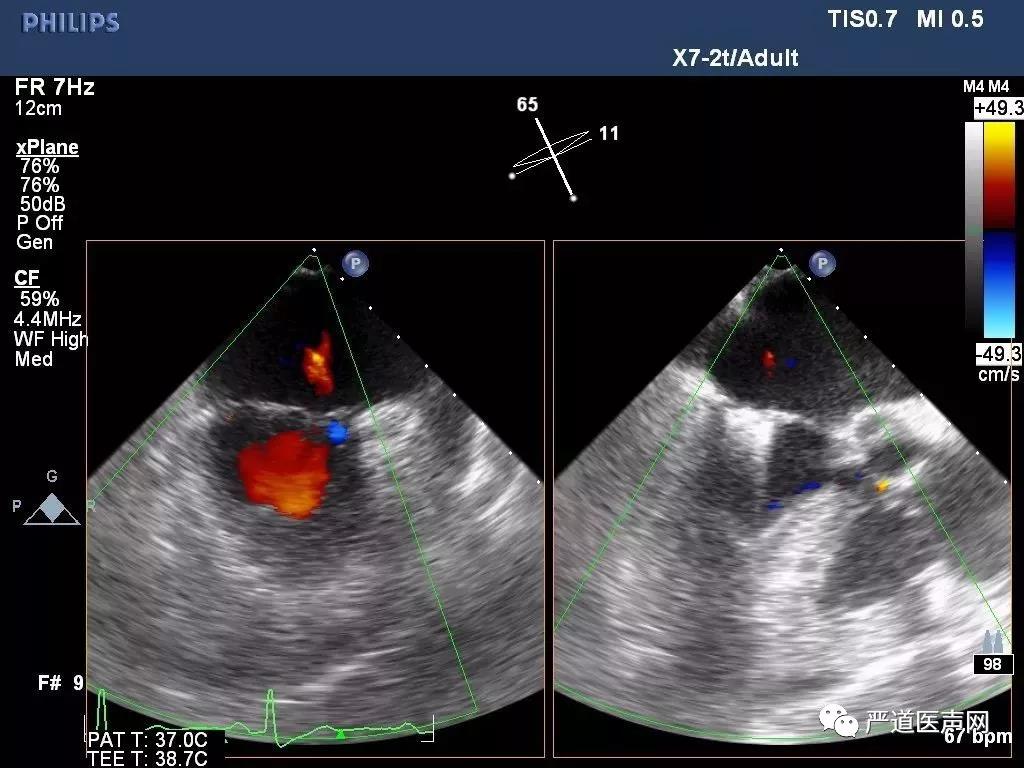

术后心超